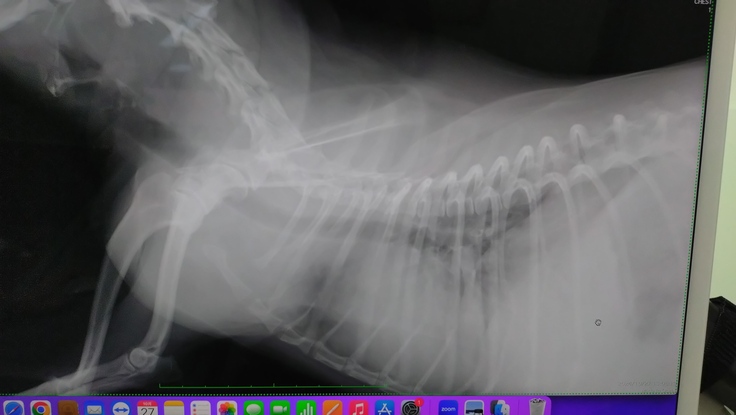

肺に転移はほぼ確定…影あり。角度によっては見えないけど、、、

喉の辺りポコポコした音は喉の痰が絡んでいる可能性が高い。

肺炎はなし。